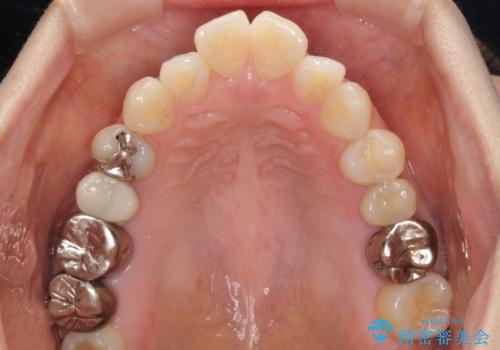

- 捻れた前歯と目立つ銀歯を気にして来院された患者様です。

歯列不正は軽微であったため、インビザライン・ライトにて改善することとしました。

左下大臼歯は根管治療が必要であったため、矯正治療前に根管治療を行い、その後矯正治療を行うこととしました。

矯正治療後には期にある銀歯を全てセラミッククラウンなどで補綴治療することとしました。

インビザライン・ライトによる矯正治療であったので、時間をかけずに治療を終えることができました。

口を開ける度に目立っていた銀歯もセラミックで自然な口元の印象となりました。